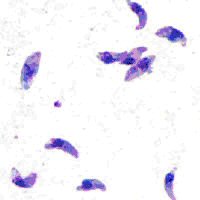

Tachyzoites of Toxoplasma gondii